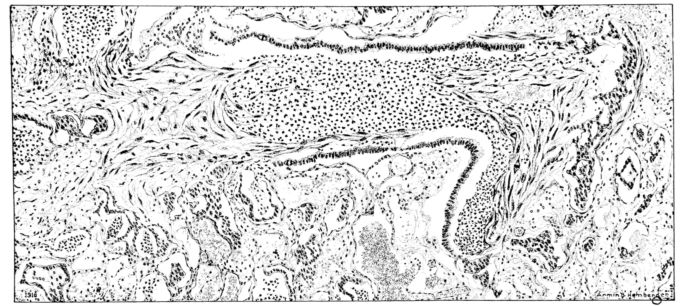

FIG. II. AUTOPSY NO. 98. DRAWING OF A SECTION THROUGH A TRACHEA SHOWING NECROTIZING HEMORRHAGIC INFLAMMATORY PROCESS OF THE MUCOSA.

The changes are less marked, perhaps, in the trachea than in its finer ramifications. The mucosa is constantly more or less destroyed and large areas, usually focal, are entirely devoid of their epithelial covering. This is replaced by a sparse exudate, composed largely of red blood cells, mucus, a small amount of fibrin, and nuclear fragments (Fig. II). It may dip into the submucosa for a short distance, but usually these indentures are associated with the ducts of the mucous glands into which the inflammatory reaction extends. A more striking feature than the exudate, however, is the edema and the congestion of the submucosa. The loose areolar tissue of the submucosa is spread widely apart, and throughout it distended blood vessels are very conspicuous. Occasionally such a vessel is broken and actual hemorrhage appears in the submucosa. Occasionally, too, the inflammation extends down the duct to the mucous gland itself, and here, also, aplastic inflammatory reaction is evident, inasmuch as the acini now stain intensely red with the cells undifferentiated from each other and specked here and there by broken remains of the dead nuclei (Fig. III). After the disease has continued for a short period, even at the end of five or six days, some regeneration of the epithelial lining may be seen (3) (Fig. IV). But despite this, the acute picture persists, and there goes on, side by side, an attempted repair characterized by epithelial regeneration and the same evidence of acute change. Since the lesion is essentially a superficial one, scars or contractures of any extent are not encountered in the trachea, even in examples of the disease that have ended fatally only after many weeks.[4]